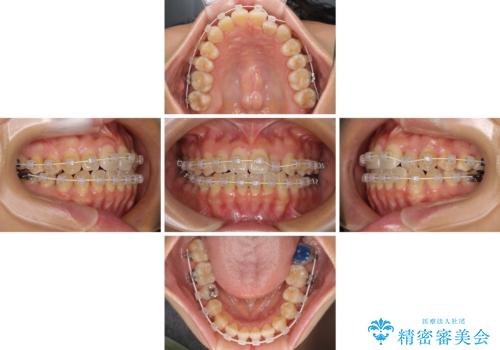

クロスバイトの前歯を改善 ワイヤー装置で楽々矯正治療

- 前歯のクロスバイトを改善したいとのことで来院された患者様です。

マウスピース矯正は自己管理が煩わしいとのことで、ワイヤー装置による矯正治療を行うこととしました。

舌の突出癖が認められたため、デコボコ改善に伴い前歯が前突する可能性があったため、舌のトレーニングをしっかりと行うよう指導しながら治療を進めることとしました。

左下の奥歯は根管治療後に放置されていたため、咬み合わせを調整しながら矯正治療を行い、最後にオールセラミッククラウンにて補綴治療を行うこととしました。

舌のトレーニングをしっかりと行っていただき、補綴治療も含めて1年強の短期間で治療を終えることができました。